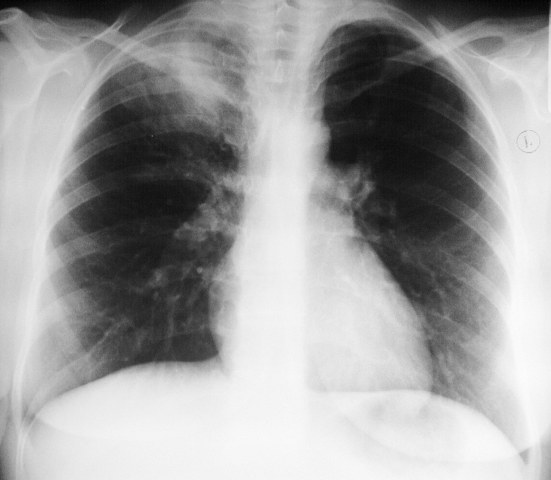

Женщина 32 года; месяц как кашляет. Повышения температутры тела не отмечала. Изначально выполнили рентгенографию. Что делать дальше?

Ок, мы определились с дифференциальным рядом при такой рентгенологической картине (Затемнение верхених сегментов правого лёгкого, S2). Какую рекоммендацию Вы бы дали такому пациенту? Что будем делать дальше?

Далее рекомендуем лабораторные исследования, КТ легких.

Давайте определимся, для начала обозначим какие КТ признаки мы видим на представленных сканах. И главное это не перечисление вариантов диагнозов (если нет однозначного варианта); а определить что надо сделать следующим этапом для достижения окончательного диагноза.

Вполне адекватная тактика. КТ контроль через 3-4 недели после антибактериальной терапии, совершенно правильно.

В данном случае, пульмонолог решил пойти на бронхоскопию; был забор материала. Лабараторный анализ (ПЦР) выявил положительную реакцию на туберкулёз.